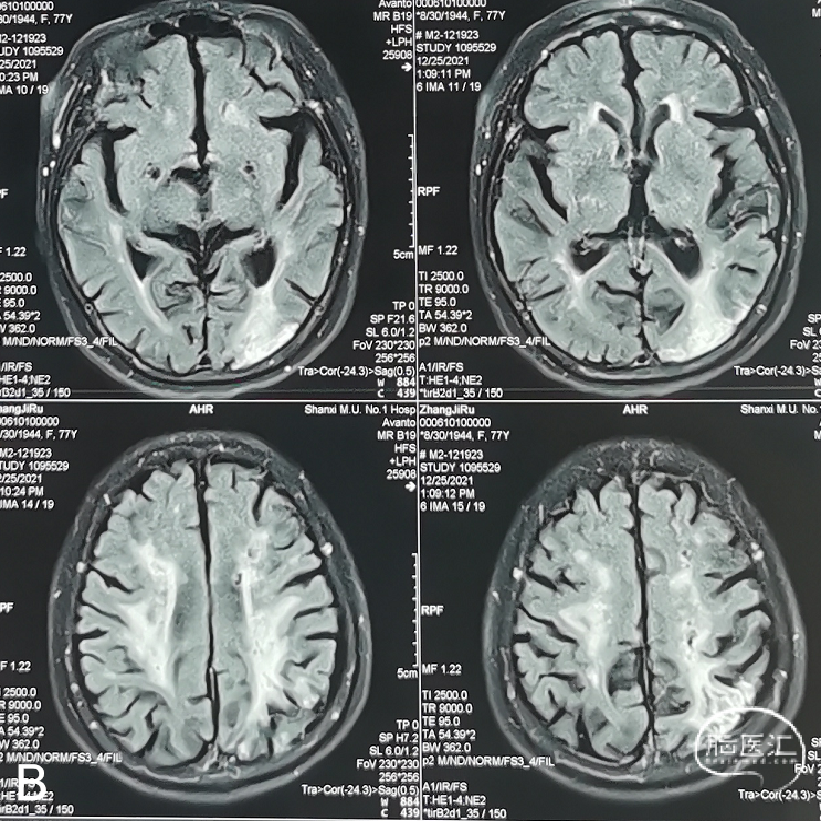

外院行头颅核磁示:左侧额顶枕叶急性脑梗死;颅内多发陈旧性脑梗死。

1. 手术指征:患者DSA示左侧颈内动脉眼动脉段重度狭窄;核磁显示左侧分水岭脑梗死